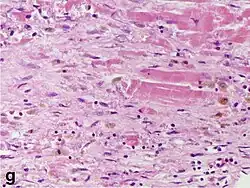

Although earlier changes can be discerned using electron microscopy, one of the earliest changes under a normal microscope are so-called wavy fibers.[23] Subsequently, the myocyte cytoplasm becomes more eosinophilic (pink) and the cells lose their transversal striations, with typical changes and eventually loss of the cell nucleus.[24] The interstitium at the margin of the infarcted area is initially infiltrated with neutrophils, then with lymphocytes and macrophages, who phagocytose ("eat") the myocyte debris. The necrotic area is surrounded and progressively invaded by granulation tissue, which will replace the infarct with a fibrous (collagenous) scar (which are typical steps in wound healing). The interstitial space (the space between cells outside of blood vessels) may be infiltrated with red blood cells.[22]

| Vessel/endothelial sprouts* | 5–10 days | 10 days–4 weeks | 4 weeks: disappearance of capillaries; some large dilated vessels persist |

| Fibroblast and young collagen* | 5–10 days | 2–4 weeks | After 4 weeks; depends on size of infarction; |

| Dense fibrosis | 4 weeks | 2–3 months | No |